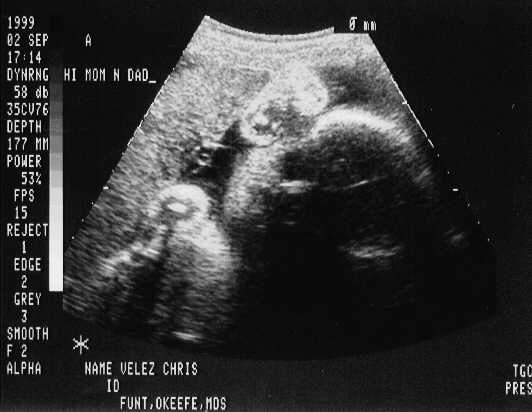

September 02, 1999 Sonograms

Kris is in her 33rd week. She can go in labor in 3 weeks!

Kristofer weighs 4.4 pounds.

The doctor says he can't believe how close they are in weight. They are almost NEVER this close in size.

Kristofer Henry

sono-0902-a1.JPG - 22.3 K